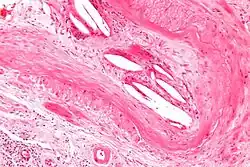

Micrograph showing a cholesterol embolus in a medium sized artery of the kidney. Kidney biopsy. H&E stain.

The microscopic examination of tissue (histology) gives the definitive diagnosis. The diagnostic histopathologic finding is intravascular cholesterol crystals, which are seen as cholesterol clefts in routinely processed tissue (embedded in paraffin wax).[7] The cholesterol crystals may be associated with macrophages, including giant cells, and eosinophils.